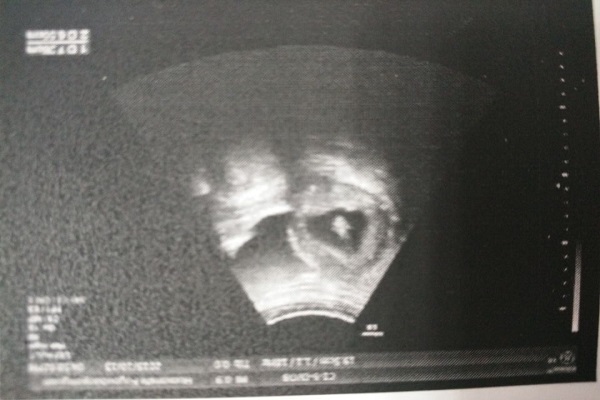

阴式B超真的有那么可怕吗?可能是你误解了,今天就来带大家了解一下两种B超的特点和区别。

【阴式B超】

从阴道探入

精准、直观,能看到子宫和附件疾病

能提前发现早早孕

【普通B超】

在腹部检查

耗时长

部分细节不清晰

对比之后可以发现,二者检查的方式不同,准确率也不同,相比之下前者更具优势,如果是宫外孕、瘢痕妊娠这种特殊情况,是不可能有时间憋尿的,普通B超太慢了,为了保障母婴安全,快速做出诊断,还是做阴超比较合适。